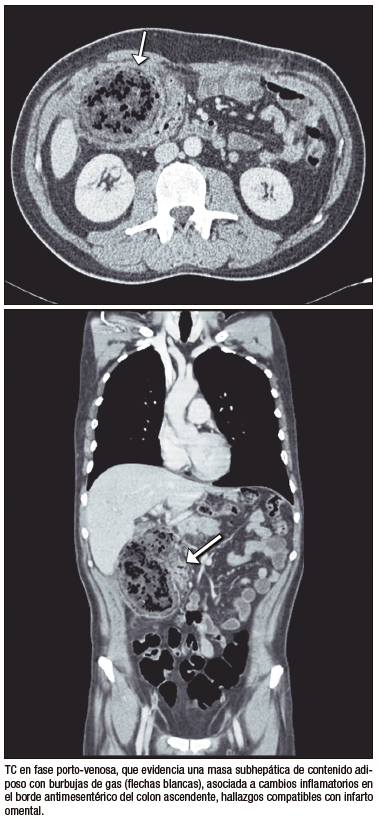

●Caso 5. Hombre de 52 años con antecedente de gastrectomía total y linfadenectomía por adenocarcinoma gástrico de células en anillo de sello. Durante el seguimiento en quimioterapia adyuvante se solicitó una TC de abdomen y pelvis, que demostró una voluminosa área de infarto en el epiplón mayor.

Entre las complicaciones tempranas, la filtración anastomótica es una de las más graves, con incidencia reportada del 1% – 10% y elevada mortalidad.5 La TC es más sensible que el tránsito baritado para detectar colecciones con gas y extravasación de contraste.6, 7 La hemorragia posoperatoria, aunque infrecuente (0,5% – 5%), constituye una emergencia vital; la TC permite detectar hematomas y extravasación activa en fase arterial.8 La fístula entero-quilosa es poco común y secundaria a lesión linfática durante la linfadenectomía; en TC puede manifestarse como líquido hipodenso o colecciones con nivel líquido-graso.9 La pancreatitis aguda posoperatoria, generalmente relacionada con manipulación quirúrgica o compromiso vascular, puede confirmarse con TC mediante la identificación de necrosis focal y cambios inflamatorios.10 Finalmente, el infarto omental se observa como una masa grasa heterogénea con estriación del tejido adiposo, simulando absceso o recurrencia tumoral.11